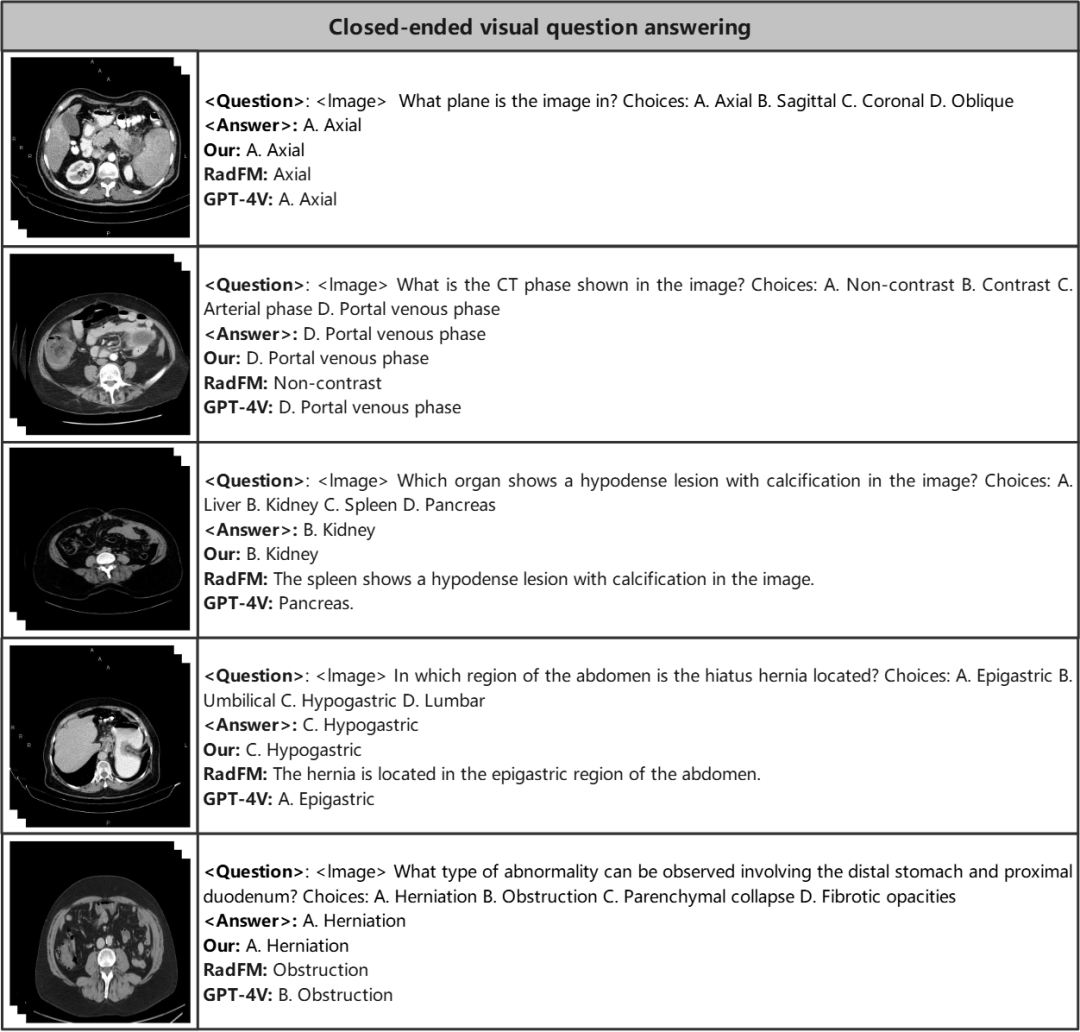

封闭式视觉问答

在封闭式视觉问答中,需要为模型提供封闭的答案候选,例如 A,B,C,D,要求模型从候选中选出正确答案。

我们发现在医学领域 M3D-LaMed 超过通用的 GPT-4V。

封闭式 VQA 测评结果